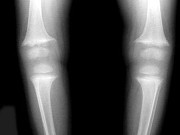

男,2岁,关节肿胀,结合图像,最可能的诊断是()

• A.肾性骨病

• B.黏多糖贮积症

• C.维生素D缺乏症

• D.维生素C缺乏症

• E.维生素D过多症